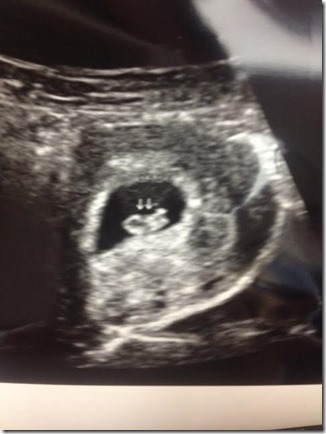

Is baby healthy? Yes! I have had three appointments and three ultrasounds! At the first one they did an ultrasound to confirm and date me, etc. Second one was at almost eight weeks to see/confirm heartbeat (145 bpm) Third one was Wednesday, they tried the doppler and couldn’t get the heartbeat so they did another ultrasound because I got nervous, baby was squirming away at 163 bpm.